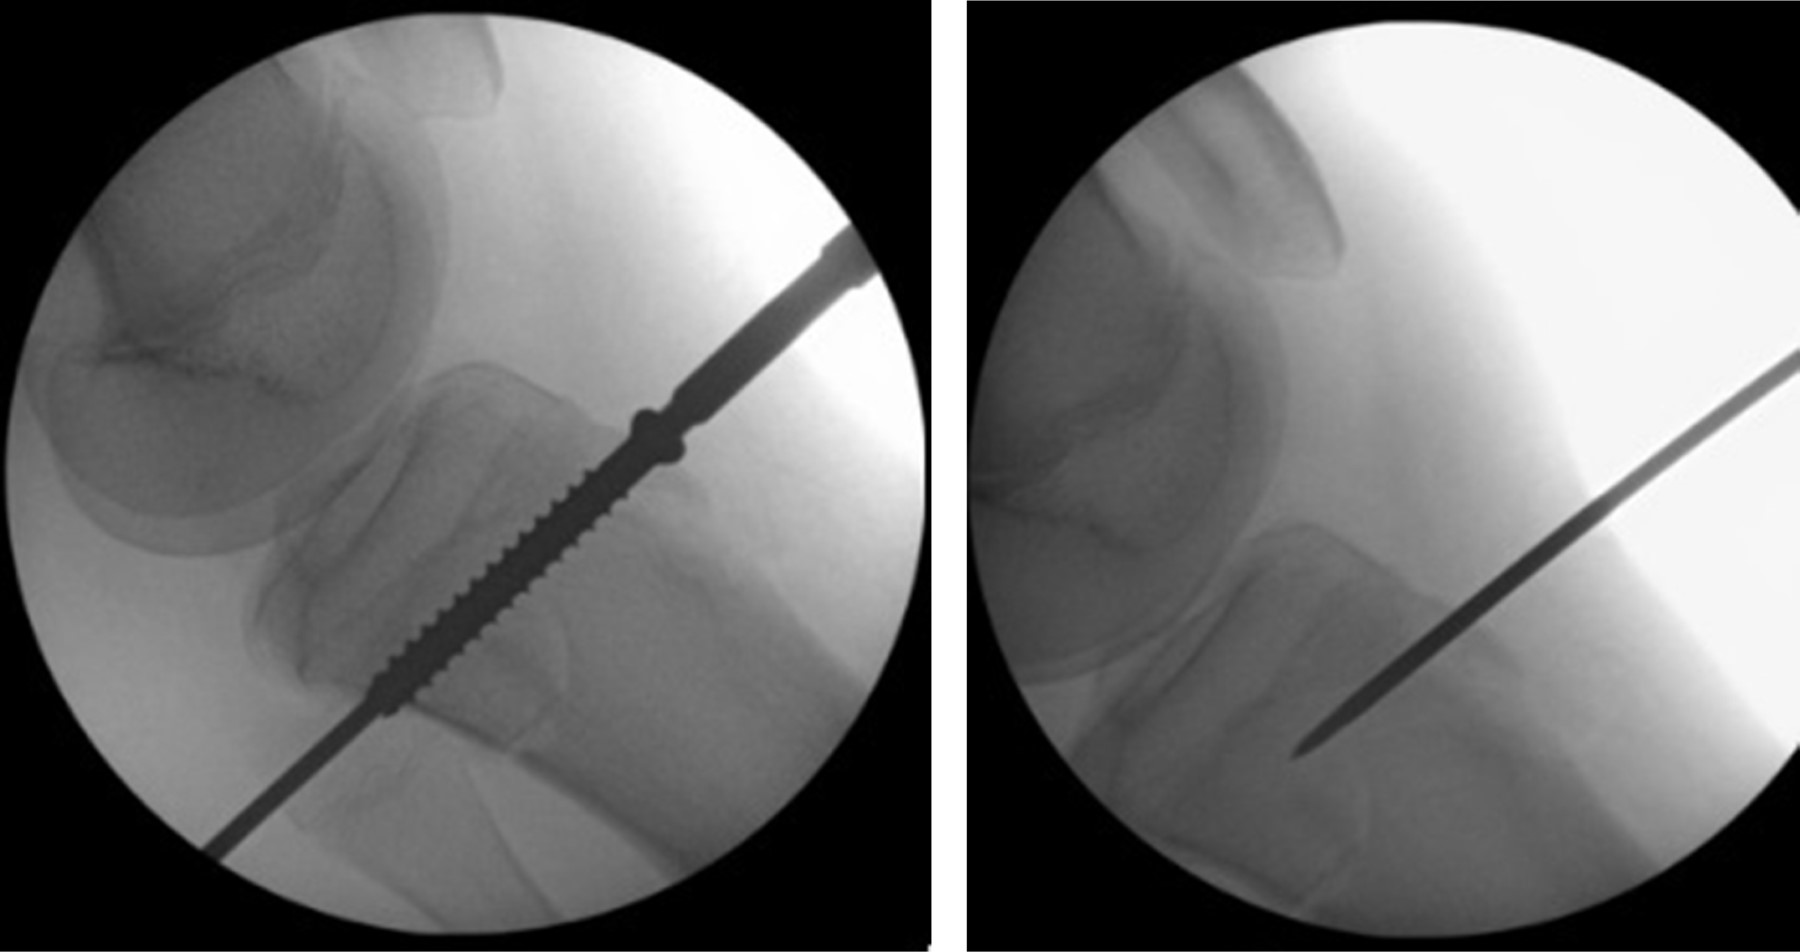

Treatment of a bilateral fracture of the anterior tubercle of the tibia in an adolescent

Fractures of the anterior tubercle of the tibia are rare pathologies that mainly affect male adolescent patients, related to sports activity, predominantly in activities that involve jumping. In patients with advanced skeletal development, the physis can be crossed by internal fixation elements; on the contrary, if the patient presents immature bone growth, we should not cross the physis because the growth cartilage could be affected. A case of an 15-year-old patient which presents a bilateral fracture of the anterior tuberosity of the tibia posterior of a fall after a low-energy jump, the patient is evaluated and treatment is indicated, with good results, in the case clinical and radiographic characteristics are described and the surgical resolution.

Figure 5